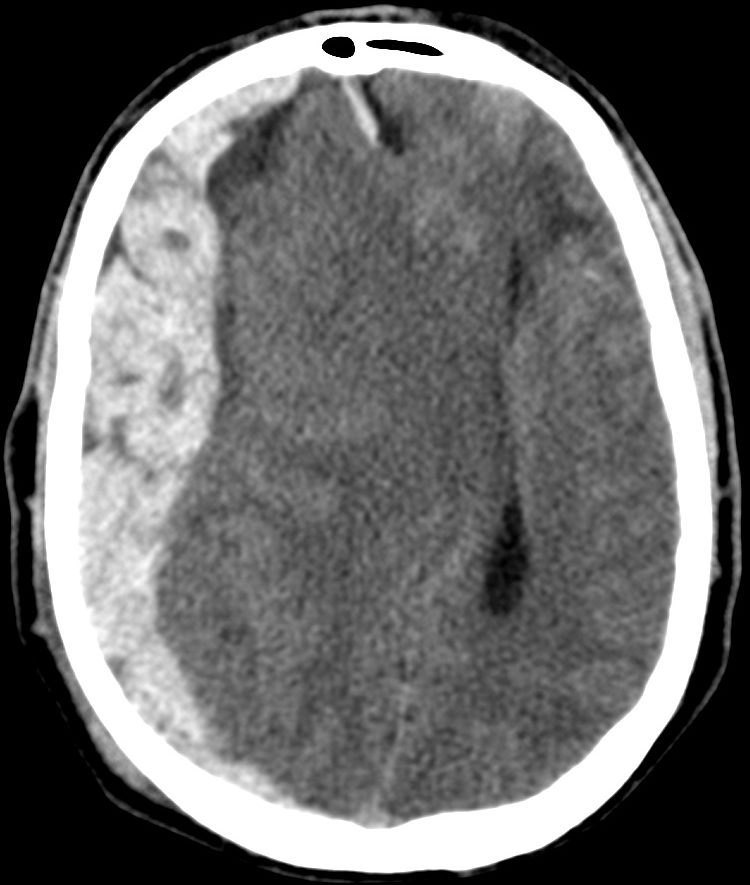

Hematoma Subdural.

- Se localiza entre la duramadre y la aracnoides y suele ser de origen venoso por la disrupción de venas corticales.

- Puede localizarse en punto de golpe y también en el de contragolpe.

- Semiluna hiperdensa (si agudo). Localización: Convexidad > hoz > tentorio

- Cuando son subagudos pasan a ser Isodensos, se identifican porque hay separación del cortex respecto a la tabla interna y efecto masa sin «masa aparente»: colpaso ventricular, desplazamiento de la línea media, etc.

- En estadío crónico puede ser hipodensos.

- Puede cruzar suturas.

- Puede asociar fracturas, contusiones, efecto masas, edema cerebral, HSA.